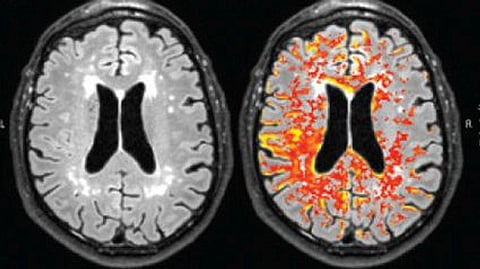

Un ACV isquémico es causado por un bloqueo en una arteria que lleva sangre al cerebro. No se encontró ninguna diferencia en el riesgo de ACV hemorrágico (provocado por un sangrado en el cerebro). Los medicamentos utilizados para tratar el TOC tampoco se vincularon con un aumento en el riesgo de accidente cerebrovascular.